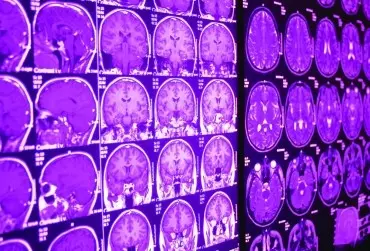

Postępowanie fizjoterapeutyczne po usunięciu guza rdzenia przedłużonego

Nowotwory ośrodkowego układu nerwowego są grupą nowotworów rozwijających się w tkankach mózgowia i rdzenia kręgowego. Jedną z podgrup w obrębie omawianych nowotworów są glejaki, czyli nowotwory wywodzące się z komórek glejowych (pełniących funkcje podporowe, odżywcze oraz naprawcze dla neuronów).